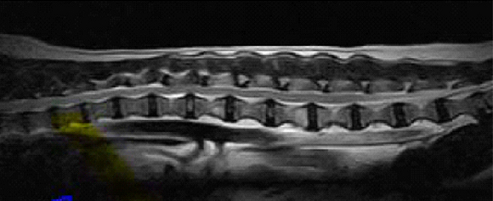

【画像診断】~ダックスフンド、雄10歳、グレート3の椎間板ヘルニア~

▲MRIのT2強調の矢状断面(キャミックに依頼)

▲椎間板ヘルニアがあるMRI像、T13-L1の造影なしのT2強調画像(キャミックに依頼)